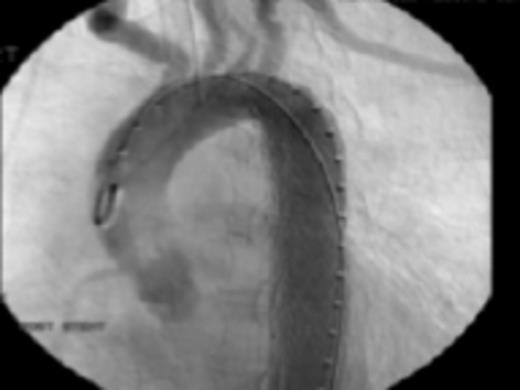

Diagnostic aortic angiography demonstrating darkening distal to the left subclavian possibly representing plaque. Image prior to stent deployment

Her past medical history of considerable GI bleeds and her significant fall risk made her a poor candidate for continued anti-coagulation therapy. The appropriateness of the lesion involved and her risk for further embolic events guided selection of endovascular technique for treatment. Exclusion was performed by a 26mm × 10cm thoracic aortic stent graft with balloon angioplasty. Post-procedure angiography confirmed position of the graft distal to the origins of the great vessels and did not demonstrate any leaks. Subsequently, she progressed well and was discharged in stable condition on warfarin and clopidogrel.